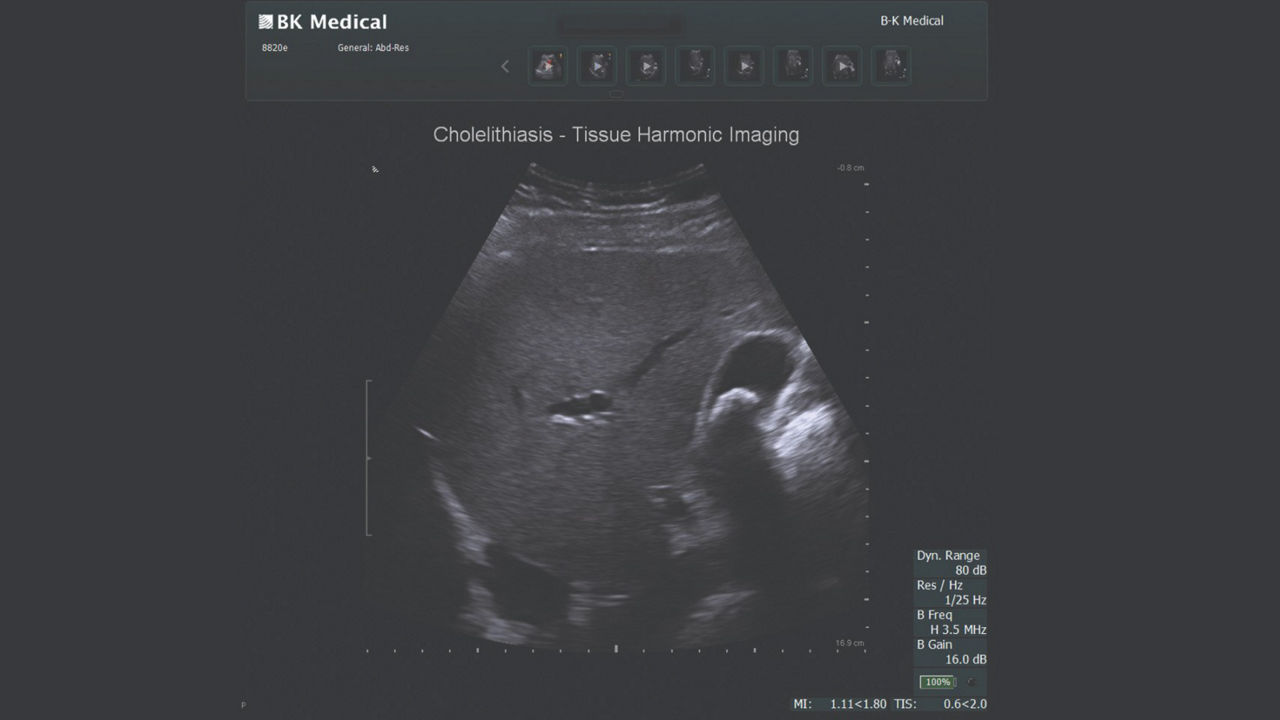

Cholecystectomy ultrasound

Active imaging with real-time intraoperative ultrasound supports fast imaging of the biliary system and is non-radiating, helping you reduce radiation hazards to your patients and staff.

Imaging to guide cholecystectomies

Discover the clinical benefits of active imaging with intraoperative ultrasound for laparoscopic cholecystectomy procedures. Using bkActiv and the Advanced Laparoscopic Transducer, surgeons can visualize anatomy and monitor progress as many times as needed during the procedure.

The value of iUS in cholecystectomies

iUS is beneficial for cholecystectomies due to its safety, quick and repeatable imaging capabilities and ability to detect choledocholithiasis and enable visualization of biliary tract anatomy.

• iUS has minimal safety risks as it is non-irradiating and does not required cannulation. ¹⁻³

• iUS can be used dynamically throughout dissection adding minimal time to a cholecystectomy procedure. iUS can also repeated, helping to assess common bile duct integrity at the end of the procedure.¹⁻⁵

• iUS helps differentiate between sludge, stone, polyps, cysts, and tumors when determining if there is a presence of gallstones in the common bile duct.⁵,⁶

• iUS uses color flow doppler to help differentiate between vessels and ducts and is overall effective at imaging difficult cases such as inflammation or fibrosis .¹,⁴⁻⁶